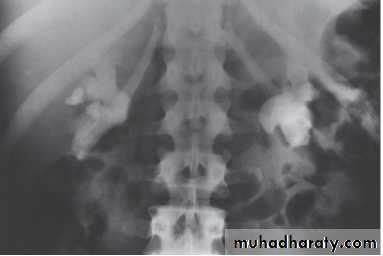

X-Ray: KUB (kidneys, ureters, bladder)

A plain radiograph of the abdomen and pelvis includes the area above both adrenal glands (lower chest) and extends to 2 cm below the symphysis pubis(includes the external genitalia)site, sex, stones, psoas shadow, skeleton, and soft tissue shadow.

Indications

1) as a primary study

2) as a scout film before contrast material injection